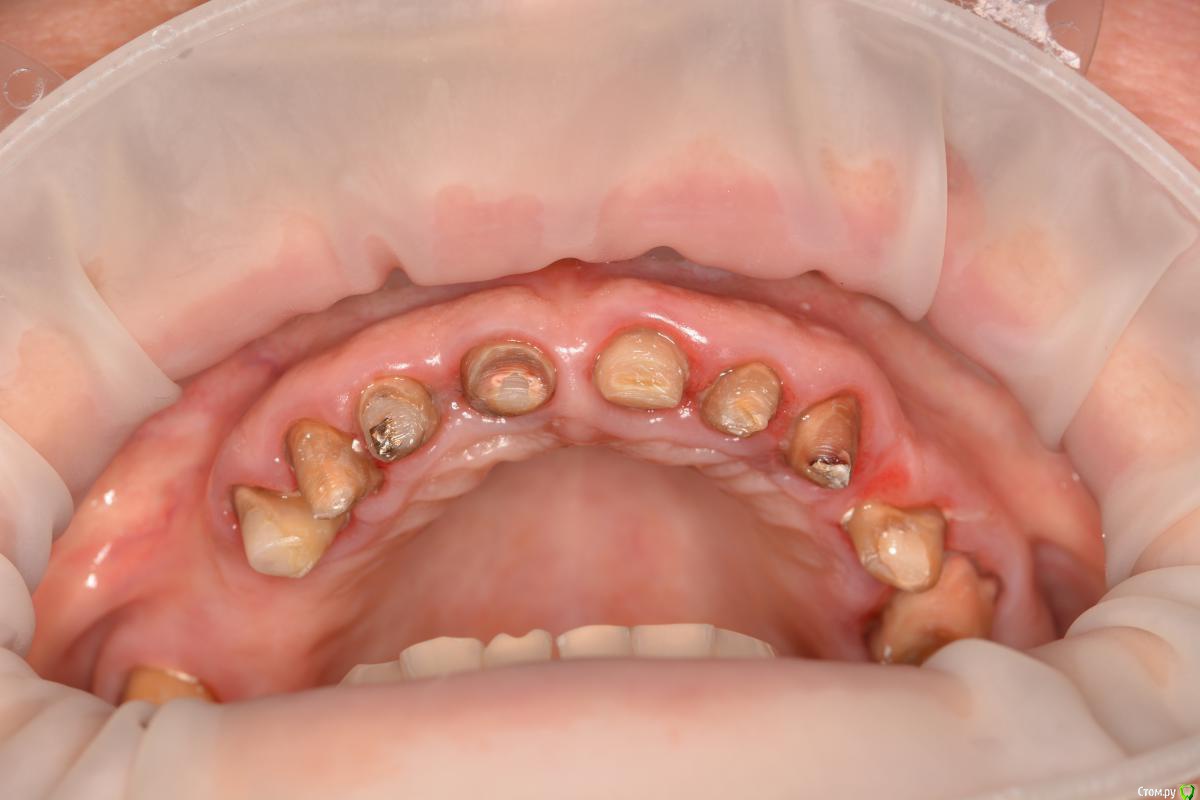

Alexandr1984 Опубликовано 29 марта, 2016 Поделиться Опубликовано 29 марта, 2016 Коллеги, что можно здесь сделать? Речь о верхней челюсти.Пациент родственник. Хотелось бы добиться наилучшей эстетики, особенно во фронте. Ранее стоял металлокерамический мост (подкова). более 15 лет. Можно ли протезировать одиночками?Мысль такая: зубы были шинированы мостом, возможно связочный аппарат частично атрофировался. Не появится ли подвижность при протезировании одиночными коронками? В 1-м сегменте планируется имплантация с синусом. Применим ли имакс к этим зубам? если да, то как фиксировать под десной по адгезивному протоколу? И что делать с темным цветом культей? заранее спасибо) Ссылка на комментарий

Freelancer1981 Опубликовано 29 марта, 2016 Поделиться Опубликовано 29 марта, 2016 (изменено) Снимки нужны,орпеделение цс,вакспа,мокап,зубы,что были под коронками придется восстанавливать,т.к.видно что перепреп,вкладки или адгезивно на стекловолокне.Можно разбить работу,сделать верх мокап длительного ношения и заняться низом,а потом перейти к верх.зубам.Тем более там планируется синус.Верхние коронки скорее всего фронт сделал бы циркон с облицовкой,если хотите эстетику. Изменено 29 марта, 2016 пользователем Freelancer1981 Ссылка на комментарий

Freelancer1981 Опубликовано 30 марта, 2016 Поделиться Опубликовано 30 марта, 2016 (изменено) если не восстанавливать культи, чем чревато? ведь при таком препе для техника будет много места играть с керамикой)если вы собираетесь делать поправильному,восстанавливать(судя по фото),длину вам нужно как минимум в 2 раза от исходной высоты культей плюс вы же еще уступы будете делать,соответственно культя будет истончаться,зубы депульпированы...чем все может закончится,знаете?))ко мне иногда приходят такие пациенты с работами в руках,сделанные где то в др.месте с остатками зубов в коронках Изменено 30 марта, 2016 пользователем Freelancer1981 Ссылка на комментарий

Карен Аванесов Опубликовано 30 марта, 2016 Поделиться Опубликовано 30 марта, 2016 С такой местами конусностью и низкой высотой культей, плюс подсыревшим местами дентином, и передавленным местами подковой пародонтом, с надежной фиксацией единичек и здоровьем пародонта будут проблемы. Все делается в комплексе. и еще как вы пресс с коффером то при такой ситуации будете фиксировать? Ссылка на комментарий